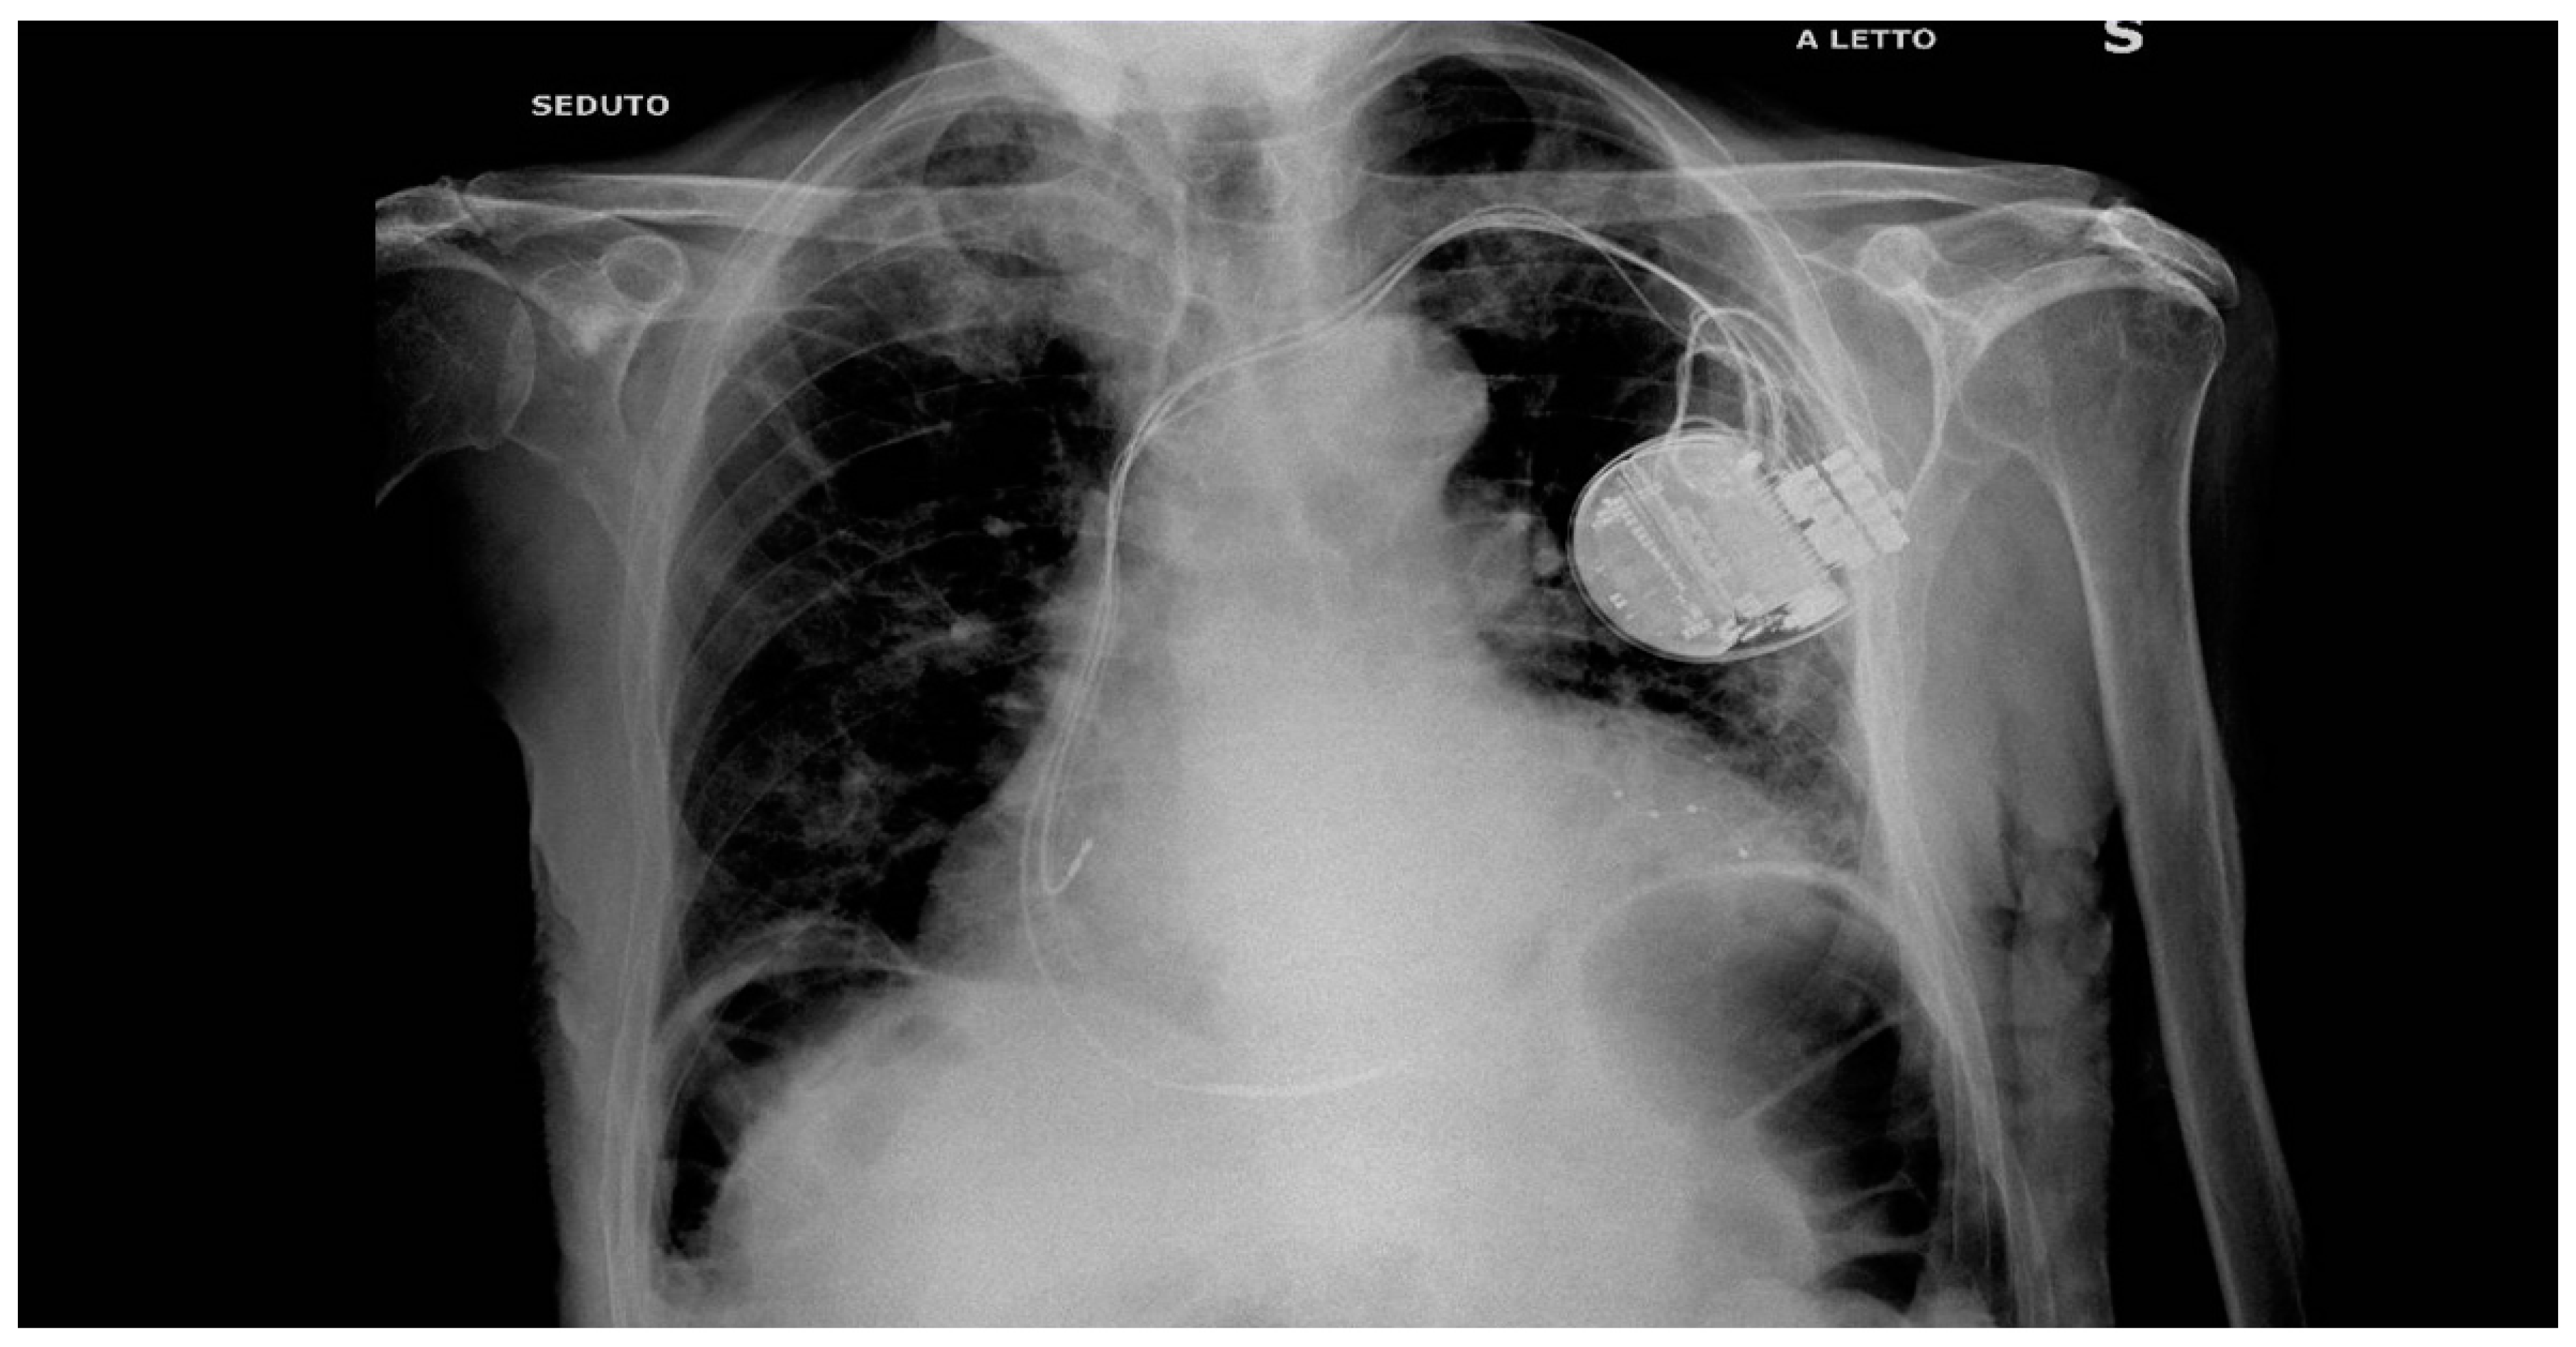

In 2022 after history of HF, hypocinetic cardiomyopathy with AF - not controlled frequency, an upgrade to CRTD implantation was programmed followed by the NAV ablation in order to reduce the elevated frequency of AF despite medical optimization (see Figure 1 for the correct position of electrocatheters after implantation). During the night, caused by an initial delirium , it has been initiated quetiapine and haloperidol in order to control the psychotic poussee. The day after the CRTD implantation, polymorphic ventricular tachycardia have been registered, initially treated with magnesium intravenously and an increment of bisoprolol dosage (see Figure 2 and Figure 3). According to the hypothesis of a proarrhythmic damage due to the new LV stimulation, a check of the device has been performed but the mechanism of CRT-induced proarrhythmia remains unknown during the LV stimulation (single site, D1-M1 configuration).

Figure 1. Thoracic Rx scan after the CRTD implantation: see the LV elettrocatheter in a postero-lateral vein of the coronary sinus. In the history of this patient has been described a coronary angioplasty of MO branch of the left circumflex.